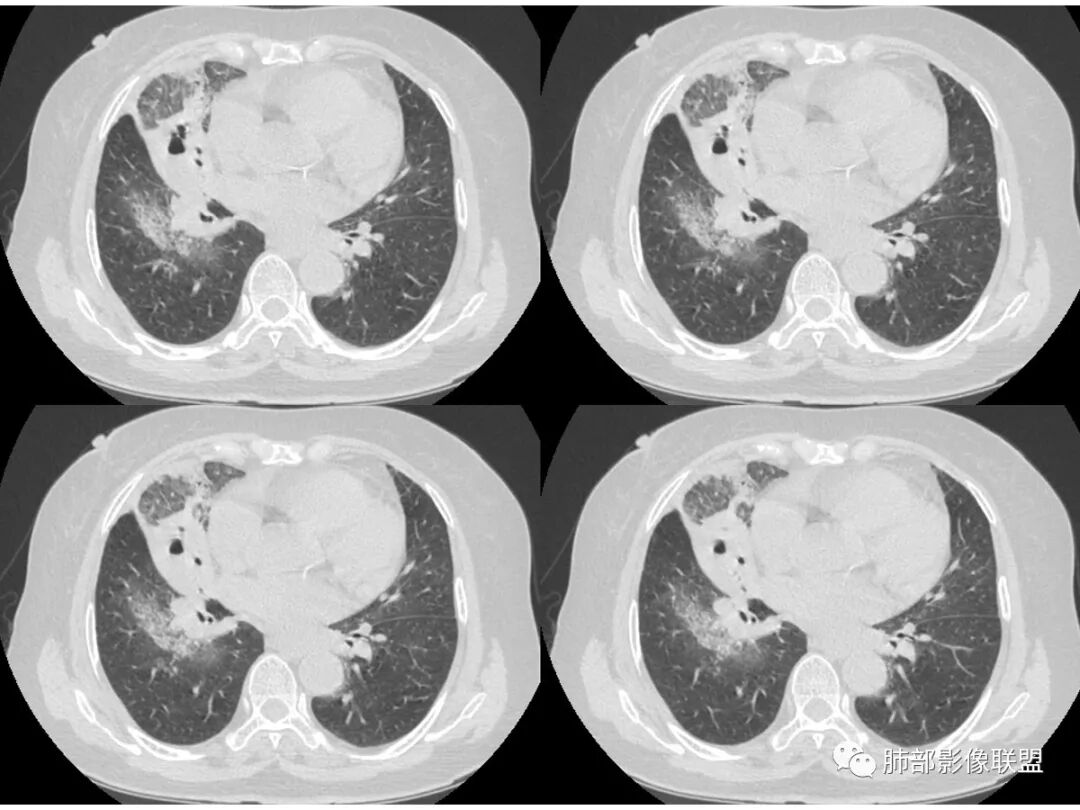

右肺上叶大片状阴影,内见僵硬的支气管,部分支气管轻度扩张,内见一空洞和液平,病灶边缘可见磨玻璃影,首先考虑恶性病变,粘液性腺癌伴感染可能。

老年女性,慢性病史,白色痰液,量多,病灶起于胸膜下,实性加磨玻璃,磨玻璃边缘偏轻,跨叶生长,病灶内可见枯树枝,考虑肺炎型肺癌。

老年女性,右肺上叶大片实变及磨玻璃密度影,磨玻璃边缘清晰,内可见小叶间隔增厚,内可见空洞,似可见分隔,叶间裂局部膨隆,纵膈窗,没有增强,枯树枝不明显,肺炎型肺癌可能,鉴别大叶性肺炎,结核?

胸CT:右肺上叶实变内可见支气管充气征,近端支气管狭窄,远端扩张,周围可见毛玻璃影,右肺中叶支气管闭塞,并可见气道壁钙化,右肺中叶体积缩小,实变内可见空洞,并可见气液平面,空洞周围可见毛玻璃样影,右肺下叶支气管开口狭窄,右肺门淋巴结肿大。纵隔窗可见病灶与壁层胸膜间隙增宽,考虑良性病变-----感染性病变------TB?

老年女性,右肺中上叶病灶,血象不高,血沉高,TB dna阴性,上叶尖端病灶,紧贴胸膜,边界似清非清,中间可见实变,内见枯树枝征,首先考虑粘液腺癌可能性大。患者右肺中叶见空洞、气液平,病灶没多发空洞,可见气液平,考虑合并TB感染。

老年女性,无诱因咳嗽咳痰,白色粘液痰,抗炎治疗无好转,右肺多叶磨玻璃影,其内见枯树枝征,磨玻璃边界清,中间见实变影,且部分实变影内见空洞或局部支气管扩张,内壁光整,无纵隔淋巴结肿大,常规考虑粘液性腺癌,感染性病变待排,细菌性的排除,白细胞不高,不太支持,建议支气管镜检。

1.右上肺大片状影,周围有磨玻璃影,支气管截断征、枯枝征、远端支气管充气征,可见多个大小不等囊泡(支气管阻塞活瓣作用形成),病灶有少许收缩力感,叶间裂被稍牵拉内移;

病史老年女,白痰;影像实变,ggo多数边界清,病灶下缘部分不清,枯树枝,支气管近端阻塞、僵硬,病灶跨叶;病灶内空洞,有液平;间质增厚有结节感;肺炎型肺癌大于干酪性肺炎。

老年女性,慢性病程,咳嗽伴白色粘液痰,无发热腹痛,糖尿病,白细胞及C反应蛋白不高,血沉快,铁蛋白高。胸部CT,右肺上叶大片状实变伴磨玻璃密度影,边界不清,边缘局部膨隆,叶裂弧形下坠,实变影宽基底与胸膜相贴;右肺下叶前基底段见类似病灶;右肺中叶不张并空洞形成,空洞内见气液平面;综合考虑右肺上叶及下叶肺炎型肺癌,右肺中叶结核。

老年女性,病史1月,右肺上中叶大片状影,跨叶,上叶为主,磨玻璃为主,边界模糊,部分实变,内见空洞影和液气平面,壁光滑,支气管开口狭窄,局部有扩张,右肺门淋巴结钙化,首先考虑感染性病变,结核可能,鉴别粘液腺癌。

老年女性,亚急性起病,右肺上中叶大片状影,跨叶,上叶为主,磨玻璃为主,边界模糊,部分实变,内见空洞影和液气平面,壁光滑,洞内可见结节形成,局部有扩张,首先考虑感染性病变,结核可能;洞内可见结节样病灶,鉴别合并曲霉、肿瘤。

薄厚不均匀,枯树枝,支气管壁僵直,叶间裂膨隆,白色粘液痰,肿瘤标志物增高,考虑粘液肺癌可能。

患者老年女性,亚急性起病,胸部CT:右肺上叶大片实变,可内见坏死性空洞,可见mGGO,GGO边缘清晰,局部彭隆,内见支气管充气征,可惜没增强,粘液腺癌要考虑,但病灶明显是内朝外不支持,综合考虑结核,建议查痰找抗酸杆菌、气管镜

老年女性,咳白色粘液痰,右肺跨叶大片高密度影,密度不均匀,其内见支气管枯树征,有空洞,边缘部分清楚,叶间裂有下坠膨隆感。考虑粘液腺癌,鉴别干酪性肺炎